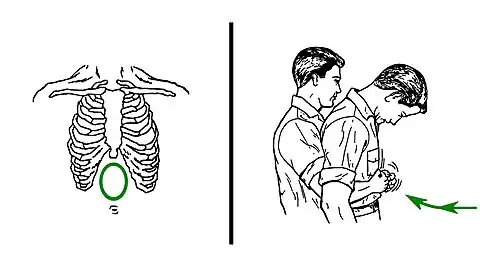

Chest thrusts

When abdominal thrusts cannot be performed on the victim (serious injuries, pregnancy, or belly size that is too large for the rescuer to effectively perform abdominal thrust technique), chest thrusts are advised instead.[39]

Chest thrusts are performed with the rescuer embracing the chest of the choking victim from behind. Then, the rescuer closes the own dominant hand and grasps it with the other hand. This can produce several kinds of fists, but any of them can be valid if it can be placed on the victim's chest without sinking a knuckle too painfully. Keeping the fist with both hands, the rescuer uses it to press forcefully inwards on the lower half of the chest bone (sternum). The pressure is not focused on the very endpoint (named xiphoid process) to avoid breaking it. When the victim is a woman, the zone of the pressure of the chest thrusts would normally be above the level of the breasts. If the first thrust does not solve the choking, it can be repeated several times.

Right: 'Chest thrusts for infants', two fingers press on the lower half of the middle of the chest.

In the chest thrusts manoeuver, the baby's body is placed lying face up on a surface (it can be the rescuer's thighs, lap or forearm). Then, the rescuer does the compressions pressing with only two fingers on the lower half of the bone that is along the middle of the chest from the neck to the belly (on the chest bone, named sternum, on its part that is the nearest to the belly). Abdominal thrusts are not recommended in children less than one year old because they can cause liver damage.[60]